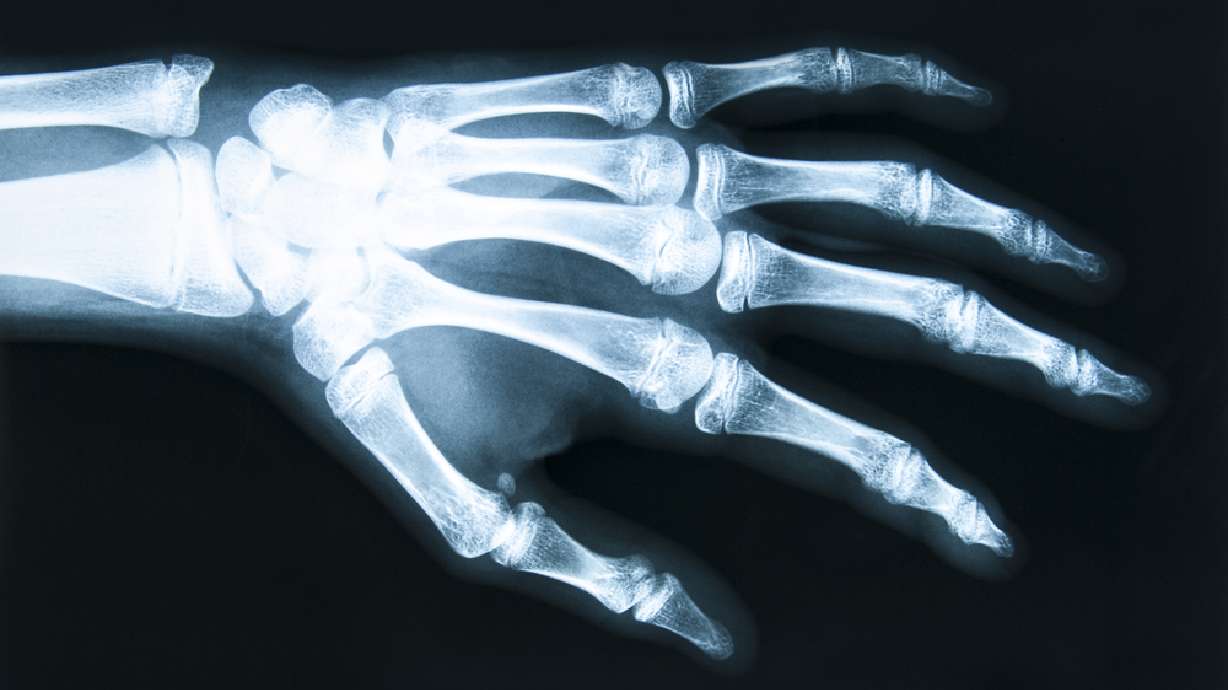

Editor's note: WARNING: The photo gallery contains graphic images. Viewer discretion is advised.CHANGSHA, China (CNN) — A man in China may regain use of his hand after it was cut off in an industrial accident. Even more amazing is how the doctors saved the man's hand: They grafted it onto his leg.

The man, who has been identified as Mr. Zhou, lost his entire left hand several weeks ago in a spinning blade machine in the factory where he was working. A surgical team, led by Dr. Tang Juyu, carried out the procedure at the Xiangya Hospital in Changsha in central China.

After about a month, the blood vessels and tendons in Zhou's arm healed and the doctors reattached the appendage to its original limb. Zhou has been reported to be able to move his fingers a little bit, and he will continue rehab to try to recover full use of the hand again.